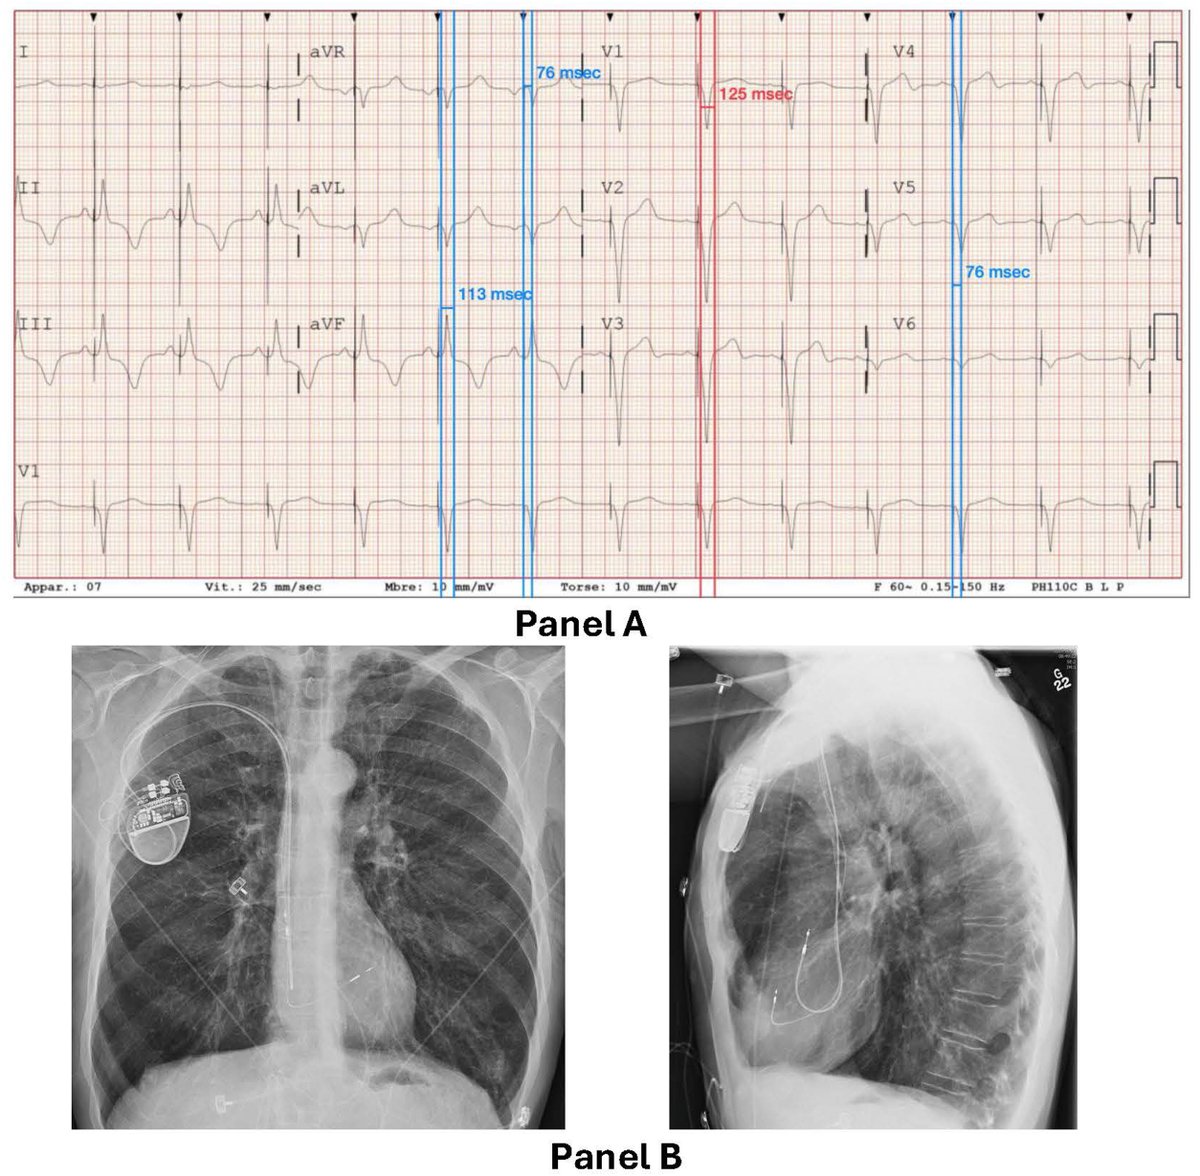

Last case at Cleveland Clinic Florida. Patient with ischemic cardiomyopathy and heart block, referred for "biventricular" ICD. #dontdissthehis instead.

Sergio Pinski tweet mediaSergio Pinski tweet mediaSergio Pinski tweet media